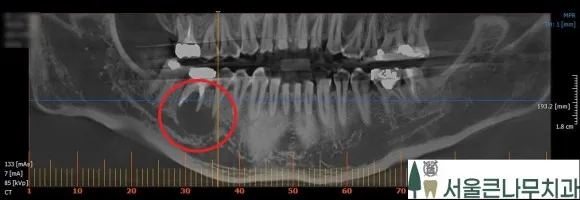

위 CBCT 사진을 보시면 더 명확히 확인할 수 있는데요. 주위 치아와는 다르게 뿌리 아래로 동그란 검은 주머니가 보이시나요? 엑스레이에서 검은 부위는 염증이라고 생각하면 됩니다. 당일 뼈이식 동반 임플란트 수술을 진행해야 합니다.

위 CBCT 사진을 통해 뼈이식 부위를 더 명확히 확인할 수 있습니다.

위 사진은 치아를 제거하기 전과 발치하고 뼈이식까지 완료한 CBCT 비교 사진입니다. 확실히 차이가 보이시죠?